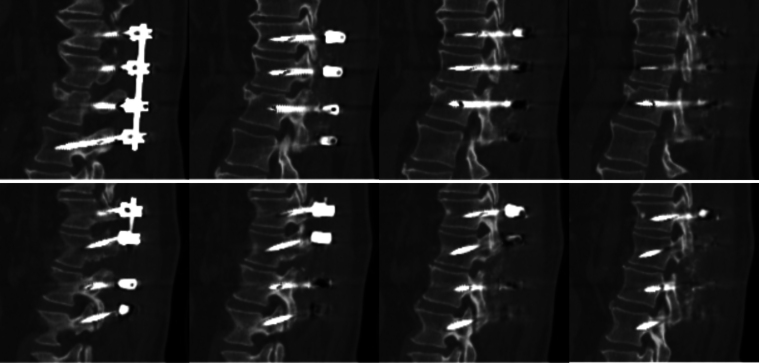

Background: Metallic implants can cause imaging artifacts on CT and MRI. Although metal artifact reduction (MAR) techniques have enhanced imaging clarity, they can also lead to distortions that may resemble complications such as hardware fractures. The false appearance of fractured hardware, or "pseudofractures," can distort imaging interpretation and result in unnecessary revision surgery.

Observations: A 65-year-old male sustained a T12-L1 fracture extending through the disc space with ligamentous interruption after a bicycle accident. The patient underwent T11-L2 posterior fusion with pedicle screws and was discharged in a thoracolumbar sacral orthosis brace after an uncomplicated postoperative course. Concerns about brace compliance prompted imaging, which demonstrated screw fractures and led to discussion of revision procedure. Repeat imaging revealed that these were artifacts, not hardware failure. No revision was needed and the patient continued to recover.

Lessons: This case emphasizes the importance of understanding imaging techniques that may impact interpretation and implications for surgical decision-making. Imaging artifacts should be considered when hardware fractures exist at multiple levels without suggestive history of new symptoms. Obtaining plain radiographs or images without MAR may assist in diagnostic uncertainty. Discussing MAR use with the radiology department at imaging acquisition may improve both imaging interpretations and resource utilization. https://thejns.org/doi/10.3171/CASE25358.